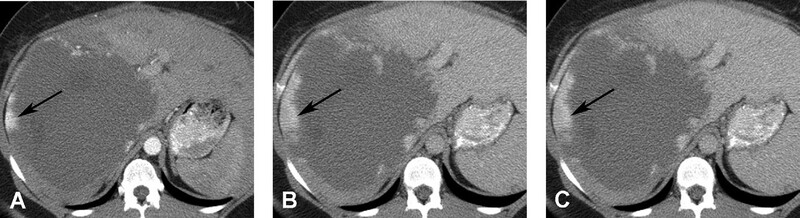

Nói chung các tổn thương nhỏ hơn lấp đầy thuốc nhanh hơn các tổn thương lớn. Các hemangioma khổng lồ, thường lớn hơn 5-10cm, có thể không lấp đầy hoàn toàn thuốc tương phản (Hình 4 và 5), và có thể tạo ra các vùng nang giới hạn rõ ở trung tâm như dịc h đơn thuần. Các tổn thương nhỏ, <1cm, có thể lấp đầy nhanh và có thể không phân biệt được với HCC hoặc di căn giàu mạch máu. Tuy nhiên, u giàu mạch máu thải thuốc nhanh, trong khi hemangioma tăng quang dai dẳng do thải thuốc chậm. Ngoài ra hemangioma còn có tín hiệu cao trên T2W với thời gian echo lớn hơn 112ms, trong khi các u ác tính không thấy tín hiệu cao. Hình ảnh thì động mạch với thời gian tối ưu cung cấp thông tin chẩn đoán quan trọng nhất để xác định đặc điểm hemangioma.

Hình 4. Hemangioma khổng lồ ở bệnh nhân nữ 42 tuổi. (A) CT thì động mạch thấy bắt quang dạng nốt ngoại vi (mũi tên). (B) thì tĩnh mạch ửa thấy nốt bắt quang tăng lên (mũi tên). (C). Bắt quang vẫn giữ nguyên như vậy ở thì muộn (mũi tên) với không lấp đầy thuốc do huyết khối và hoại tử mạnh.